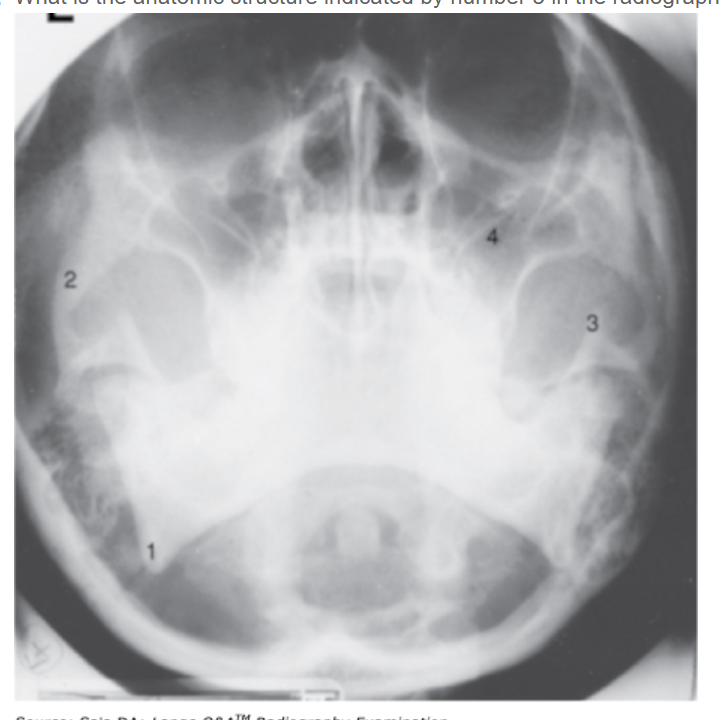

What is the anatomic structure indicated by number 3 in the radiograph in Figure 6–20?

B - Coronoid process

A parietoacanthial projection (Waters position) of the skull is shown. The chin is elevated sufficiently to project the petrous ridges below the maxillary sinuses. The zygomatic arch is well demonstrated, as are the mandible, its angle, and the coronoid process. The coronoid process corresponds to the structure labeled number 3.

What is the anatomic structure indicated by number 1 in the radiograph shown in Figure 6–20?

A - Mandibular angle

A parietoacanthial projection (Waters position) of the skull is shown. The chin is elevated sufficiently to project the petrous ridges below the maxillary sinuses (number 4). Note that the foramen rotundum is seen near the upper margin of the maxillary sinuses. Other paranasal sinus groups are not well visualized in this position, although a modification with the mouth open may be taken to demonstrate the sphenoidal sinuses. This is also the single best projection to demonstrate the facial bones. The zygomatic arch (number 2) is well demonstrated; the mandible, its angle (number 1), and the coronoid process (number 3) are also well demonstrated. The odontoid process is seen projected through the foramen magnum. The mastoid air cells are seen adjacent to the mandibular angle as multiple small, air-filled, bony spaces.

Which of the following structures is illustrated by the number 2 in Figure 2–21? A - Maxillary sinus B - Coronoid process C - Zygomatic arch D - Coracoid process

C - Zygomatic arch The parietoacanthial projection (Waters method) demonstrates a distorted view of the frontal and ethmoidal sinuses. The maxillary sinuses (number 4) are well demonstrated, projected free of the petrous pyramids. This is also the best single position for the demonstration of facial bones. The mandibular angle is illustrated by number 1, the zygomatic arch by number 2, and the coronoid process by number 3.